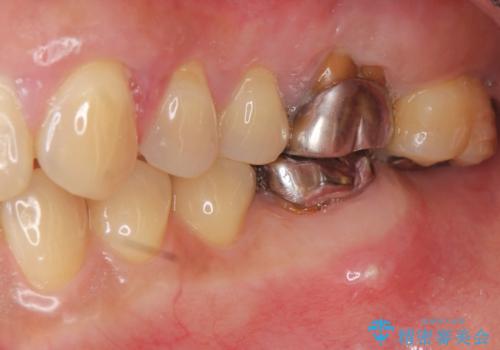

歯周病に対する全体治療

- 近医で「重度の歯周病です、入れ歯にする必要がある。」、と言われ入れ歯以外の方法がないか相談にみえられました。

再生治療、歯周外科を行うことで歯周病治療を行い、残すことのできる歯の歯周環境を整える。

残すことのできない歯は抜去したのち骨造成を含めたインプラント治療を行い、しっかりとした咬合関係を確立していきます。